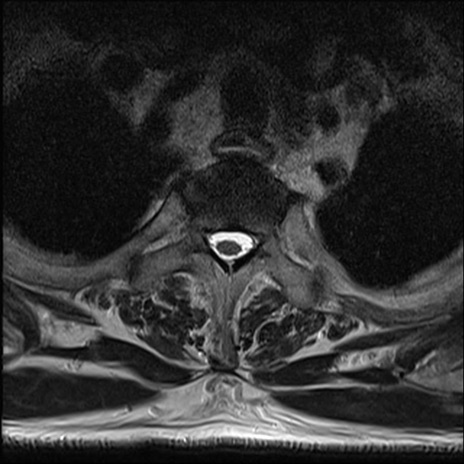

【整形】TIPS症例7 頚椎MRI T2WI(横断像)

頚椎MRI

矢状断像と横断像